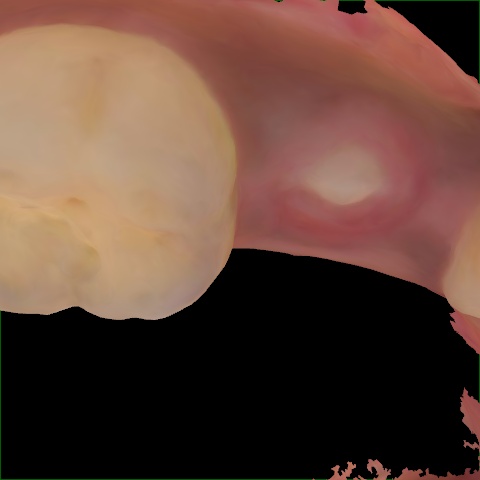

Image 385 / 1715

NHD35761

Annotated as "Good"

Original Image Rendering Image